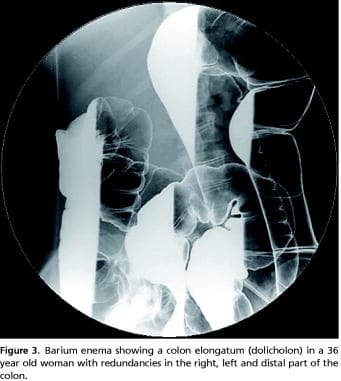

A barium enema of the colon was used to picture the anatomy and pathological changes. Colonic redundancies were recorded according to the following criteria: A sigmoid loop rising over a line between the iliac crests [9], a transverse colon below the same line and extra loops at the left and right colon flexure, are each considered to be redundant. A fully developed dolichocolon (elongated colon) occurs when all redundancies are present simultaneously [9,10]. Endoscopy was used only in patients with alarm symptoms.

Two hundred and thirty-six patients (206 females, 30 males) had a barium enema study of the colon with special reference to the number of redundancies (Figure 3).

A redundancy localized to the sigmoideum occurred in 72.5% of all patients, to the splenic flexure in 26.6%, to the tranverse colon in 33.9% and to the right hepatic flexure in 18.6%. Coecal dystopia was seen in 8.1%. The mean CTT in patients without redundancies was 36.26 h; with one redundancy, 43.80 h; with two redundancies, 41.65 h; and with three to four redundancies, 52.27 h. A Jonckheere-Terpstra test showed statistical significant differences in CTT between the four levels of redundancies (p = 0.030). A separate analysis showed a significant positive correlation between CTT and a redundant sigmoid, r = 0.147, p = 0.038). A significant increase in occurrence of the symptom variables bloating, abdominal pain and infrequent defecations was seen with and increased number of redundancies (n = 235, p < 0.01). The number of redundancies was not associated with defecation ease, incompleteness, repetitiveness and faecal consistency. Similar cross-tabulations of the physical signs did not show any significant correlations to colonic redundancies.

To date, colonic length has not been considered as a significant factor in constipation [16]. However, CTT increases with the number of colonic redundancies (colon length), which aggravated bloating, abdominal pain, and infrequent defecations. This correlation is in line with the older studies, in which a redundant colon was associated with marked constipation, pain and gas [6, 9]. The incidence of a redundant colon is low [6, 9], but higher percentages have been found in studies of colonic adenomas [17].